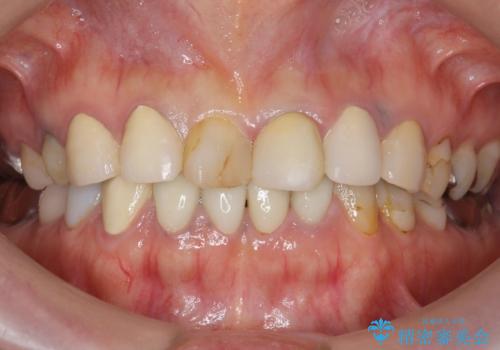

根管治療により痛みがなくなり、ご安心頂けました。

セラミッククラウンの自然な仕上がりにも喜んで下さいました。

クラウンの種類:オールセラミッククラウン エコノミー